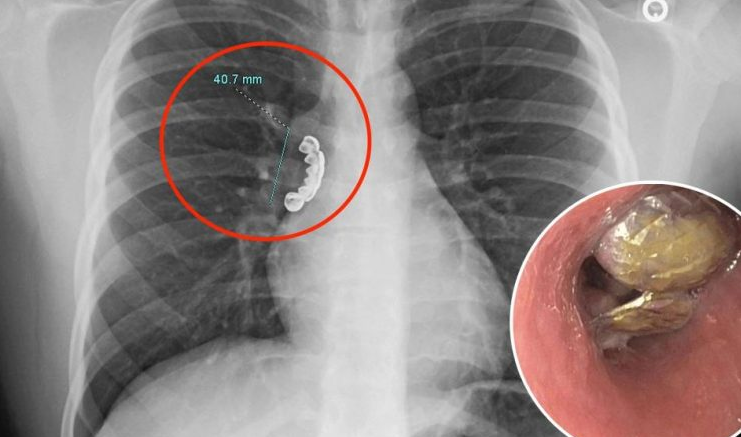

علق طاقم أسنان فضية في رئة شاب يبلغ من العمر 22 عامًا من ولاية ويسكونسن الأمريكية، بعد ابتلاعه بالخطأ.

وفي التفاصيل، أصيب رجل بنوبة صرع وكاد أن يختنق حتى الموت، حيث كان يعاني من سعال شديد وأزيز عند التنفس.

وعلى الفور، تم نقله إلى المستشفى حيث تم تصويره بالأشعة السينية، وكشف عن وجود طقم أسنان 1.5 بوصة عالق في مجرى الهواء في رئته، وفقًا لدراسة الحالة التي نُشرت هذا الأسبوع في مجلة Cureus الطبية.

وسارع الأطباء إلى الشاب لإجراء تنظير القصبات لإزالة الجسم باستخدام أنبوب مرن تم وضعه في حلق الرجل.

ونجح الأطباء في إخراج الأسنان الاصطناعية من مجرى الهواء في رئته، لكنه يعاني من تشنج قصبي، حيث تتقلص عضلات مجرى الهواء في الرئة، جراء العملية، وفقًا لصحيفة Jam Press.